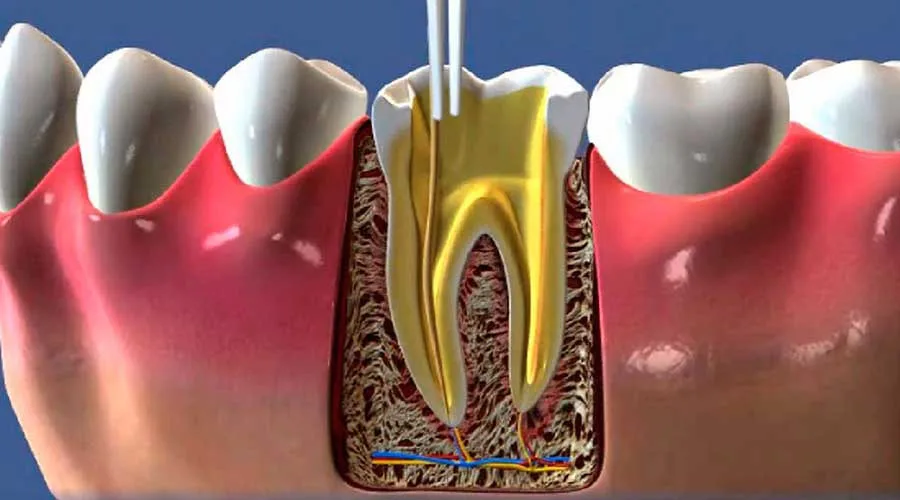

A endodontia é o tratamento odontológico especializado focado na remoção da polpa dentária infectada ou inflamada. Este procedimento é essencial para a saúde bucal, pois promove a desinfecção profunda dos canais radiculares no cotidiano.

O foco principal é salvar dentes que sofreram traumas ou cáries profundas. Ao tratar a polpa, o dentista impede que infecções se espalhem para o organismo, protegendo o paciente de complicações sistêmicas e abscessos.

A tecnologia moderna permite que a endodontia seja realizada de forma rápida e precisa. O uso de microscopia e localizadores apicais torna as etapas do processo nítidamente mais confortáveis e seguras para o paciente.

O fluxo do tratamento envolve etapas coordenadas para assegurar a limpeza completa do canal. O dentista realiza avaliações clínicas e radiográficas detalhadas antes de iniciar a desinfecção e o selamento dos canais.